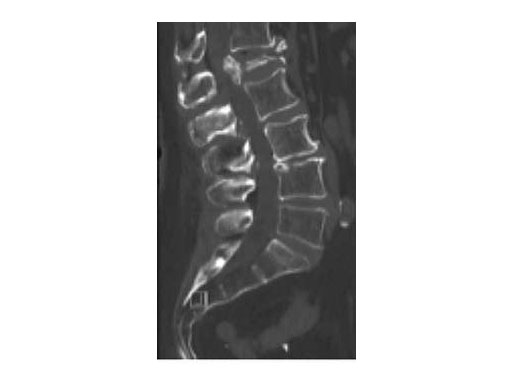

A 78-year-old woman was affected by steroid induced osteoporosis. She had persisting pain (mechanic and muscular) due to static imbalance (hyperkyphosis) and nonunion 8 months after a minor trauma with a vertebral compression fracture and vertebra plana of L1, and development of symptomatic stenosis of the spinal canal with loss of mobility over time. Pre-existing degenerative lumbar scoliosis was increased by the fracture.